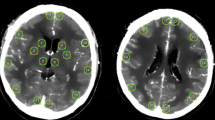

UPI data were analyzed offline by using VueBox 4.3 (Bracco Imaging, Geneva, Switzerland). A complete examination consisted of two single UPI examinations, one performed from the left side and one performed from the right side. Time to peak (TTP) and mean transit time (MTT) were quantified in four regions of interest (ROIs) per UPI examination: BG of the ipsilateral and contralateral hemisphere and anterior and posterior MCA territory of the contralateral hemisphere. Therefore, a complete examination resulted in eight ROIs to be analyzed (Fig. 1a).

Illustration of the workflow of examined patients (a) and region of interests that were evaluated by postprocessing offline analysis (b). The graphs represent ultrasound perfusion measurements after normalization with the corresponding midline region for TTP (c) and MTT (d). MCA, middle cerebral artery, Mid, midline region, MTT, mean transit time, SAH, subarachnoid hemorrhage, TTP, time to peak

Perfusion Midline Region Measurements Normalize Interpatient Variance

First, we benchmarked the robustness of the various UPI parameters across patients and measurements, which uncovered a strong interpatient and intrapatient variance of MTT and TTP values (Fig. 2a–d). To normalize multiple measurements, we used a relatively stable quotient of the right and left perfusion at the midline region ROI (Fig. 1b). Across all examinations, a strong correlation of the midline region ROI was found (R2 = 0.72, p < 0.001) for the TTP measurements but not for the MTT measurements (Fig. 1c–d). Based on the fact that MTT measurements revealed considerably more susceptible to disturbances during normalization and did not show robust measurements within multiple examinations we focused on TTP measurements in the further analysis. In the following sections, we refer to TTP as normalized TTP values.

The interpatient variance of TTP (a) and MTT (b) values for the middle cerebral artery territories. In addition, intrapatient variance of TTP (c) and MTT (d) values are displayed. The variance of the MTT values is increased compared with TTP values. MCA, middle cerebral artery, MTT, mean transit time, TTP, time to peak